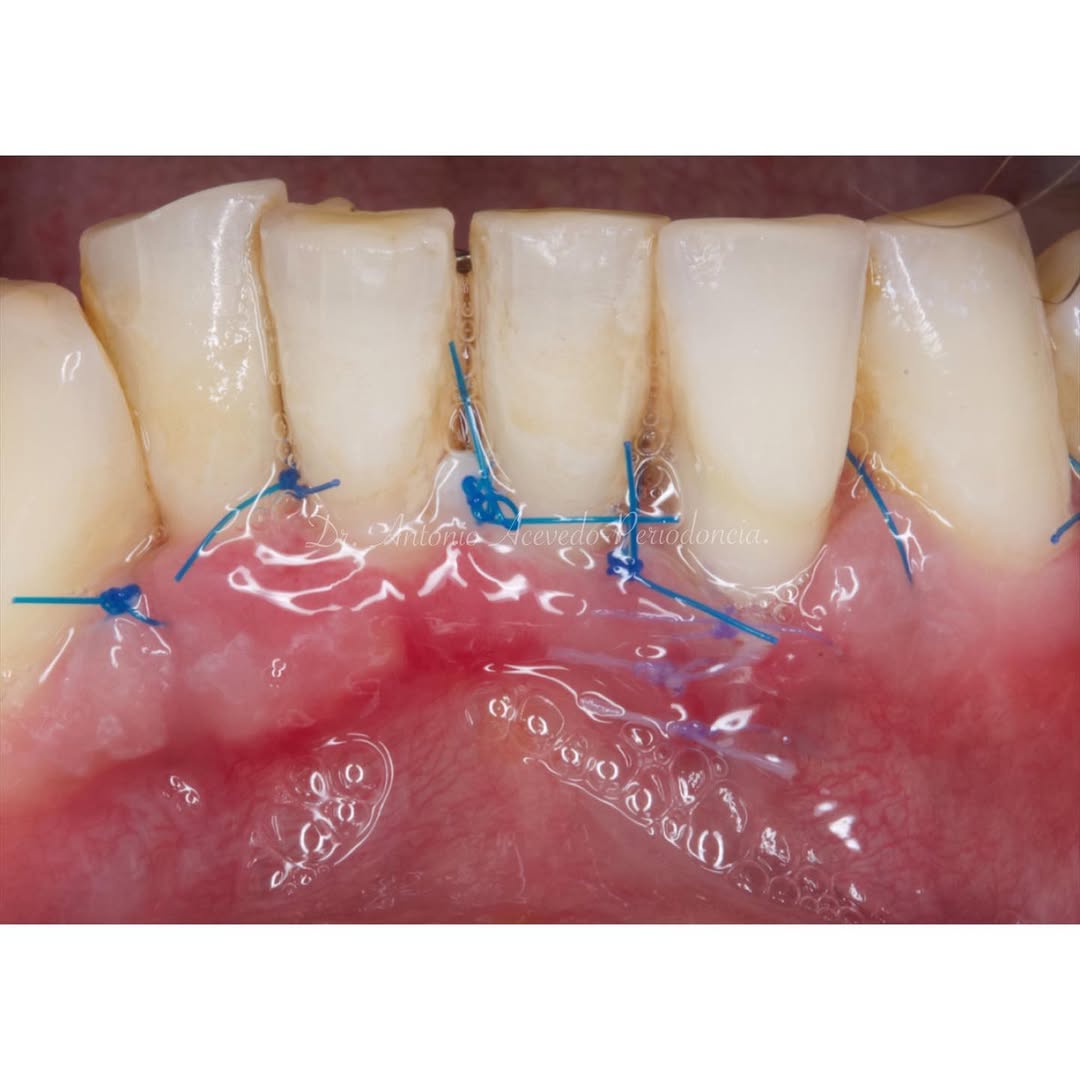

Durante una mañana, asistirás a una Cirugía Mucogingival de recubrimiento radicular de recesiones múltiples en IV y V sextante (36 a 43).

Se realizará todo el procedimiento con un microscopio operatorio, lo que permite al alumno ver toda la cirugía en directo en una pantalla en la sala de cirugía.

Aprende la planificación y técnica de la cirugía Mucogingival para el recubrimiento de recesiones y aumento de banda queratinizada en el sector anteroinferior

¡Reserva tu plaza para nuestra Estancia Clínica en Cirugía Mucogingival! 🦷

El próximo 29 de abril, abrimos las puertas de nuestra clínica para una jornada de aprendizaje intensivo “en directo”.

✅ El Reto: Recesiones gingivales en el tercer sextante.

✅ La Solución: Manejo de los LACs y

Durante una mañana, asistirás a una Cirugía Mucogingival de recubrimiento radicular de una recesión unitaria en 31 con frenillo asociado. Gracias al uso del microscopio y a la proyección en tiempo real en pantalla, verás exactamente lo mismo que veo yo durante la cirugía, sin tener que estar

Una estancia clínica pensada para quienes quieran iniciarse o dar un paso más en el campo de la cirugía mucogingival. Durante esta experiencia tendrás la oportunidad de aprender en directo cómo se planifica y se lleva a cabo una cirugía mucogingival mediante técnica de Túnel.

Formación teórico-práctica completa sobre las técnicas más avanzadas en cirugía mucogingival. Durante dos días intensivos, los participantes aprenderán desde la evidencia científica y la anatomía de las zonas donantes hasta la ejecución de injertos, cubrimiento radicular y aumento de